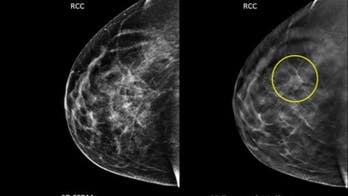

Breast Cancer - Page 37